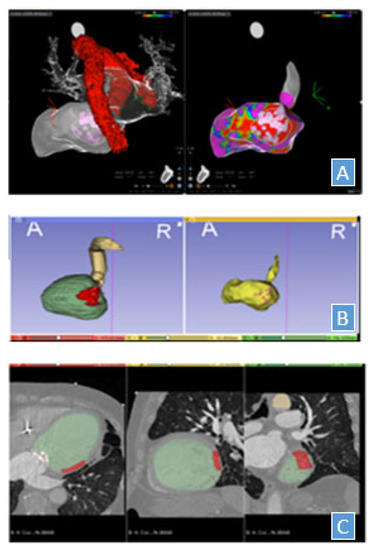

3. Target Volume Definition and Imaging Management